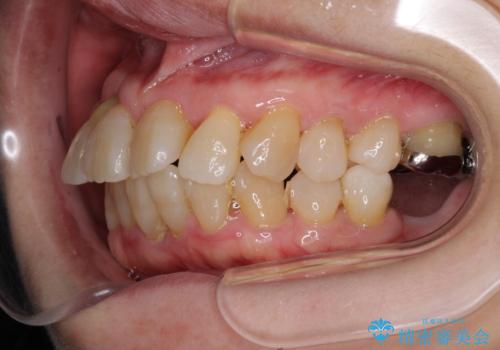

- 歯の欠損や歯肉からの出血などを気にして来院された患者様です。

診査の結果、歯周病であることが分かり、抜歯が必要な歯も見受けられました。

骨造成やインプラント、歯周外科、歯肉移植、矯正など、多くの処置を組み合わせて治療を行うこととしました。

数多くの外科処置を行ったため、治療期間は長期間となりました。

一方、外科処置をしっかりと行ったことで、歯周病の状態は改善され、安定した状態にしあげることができました。